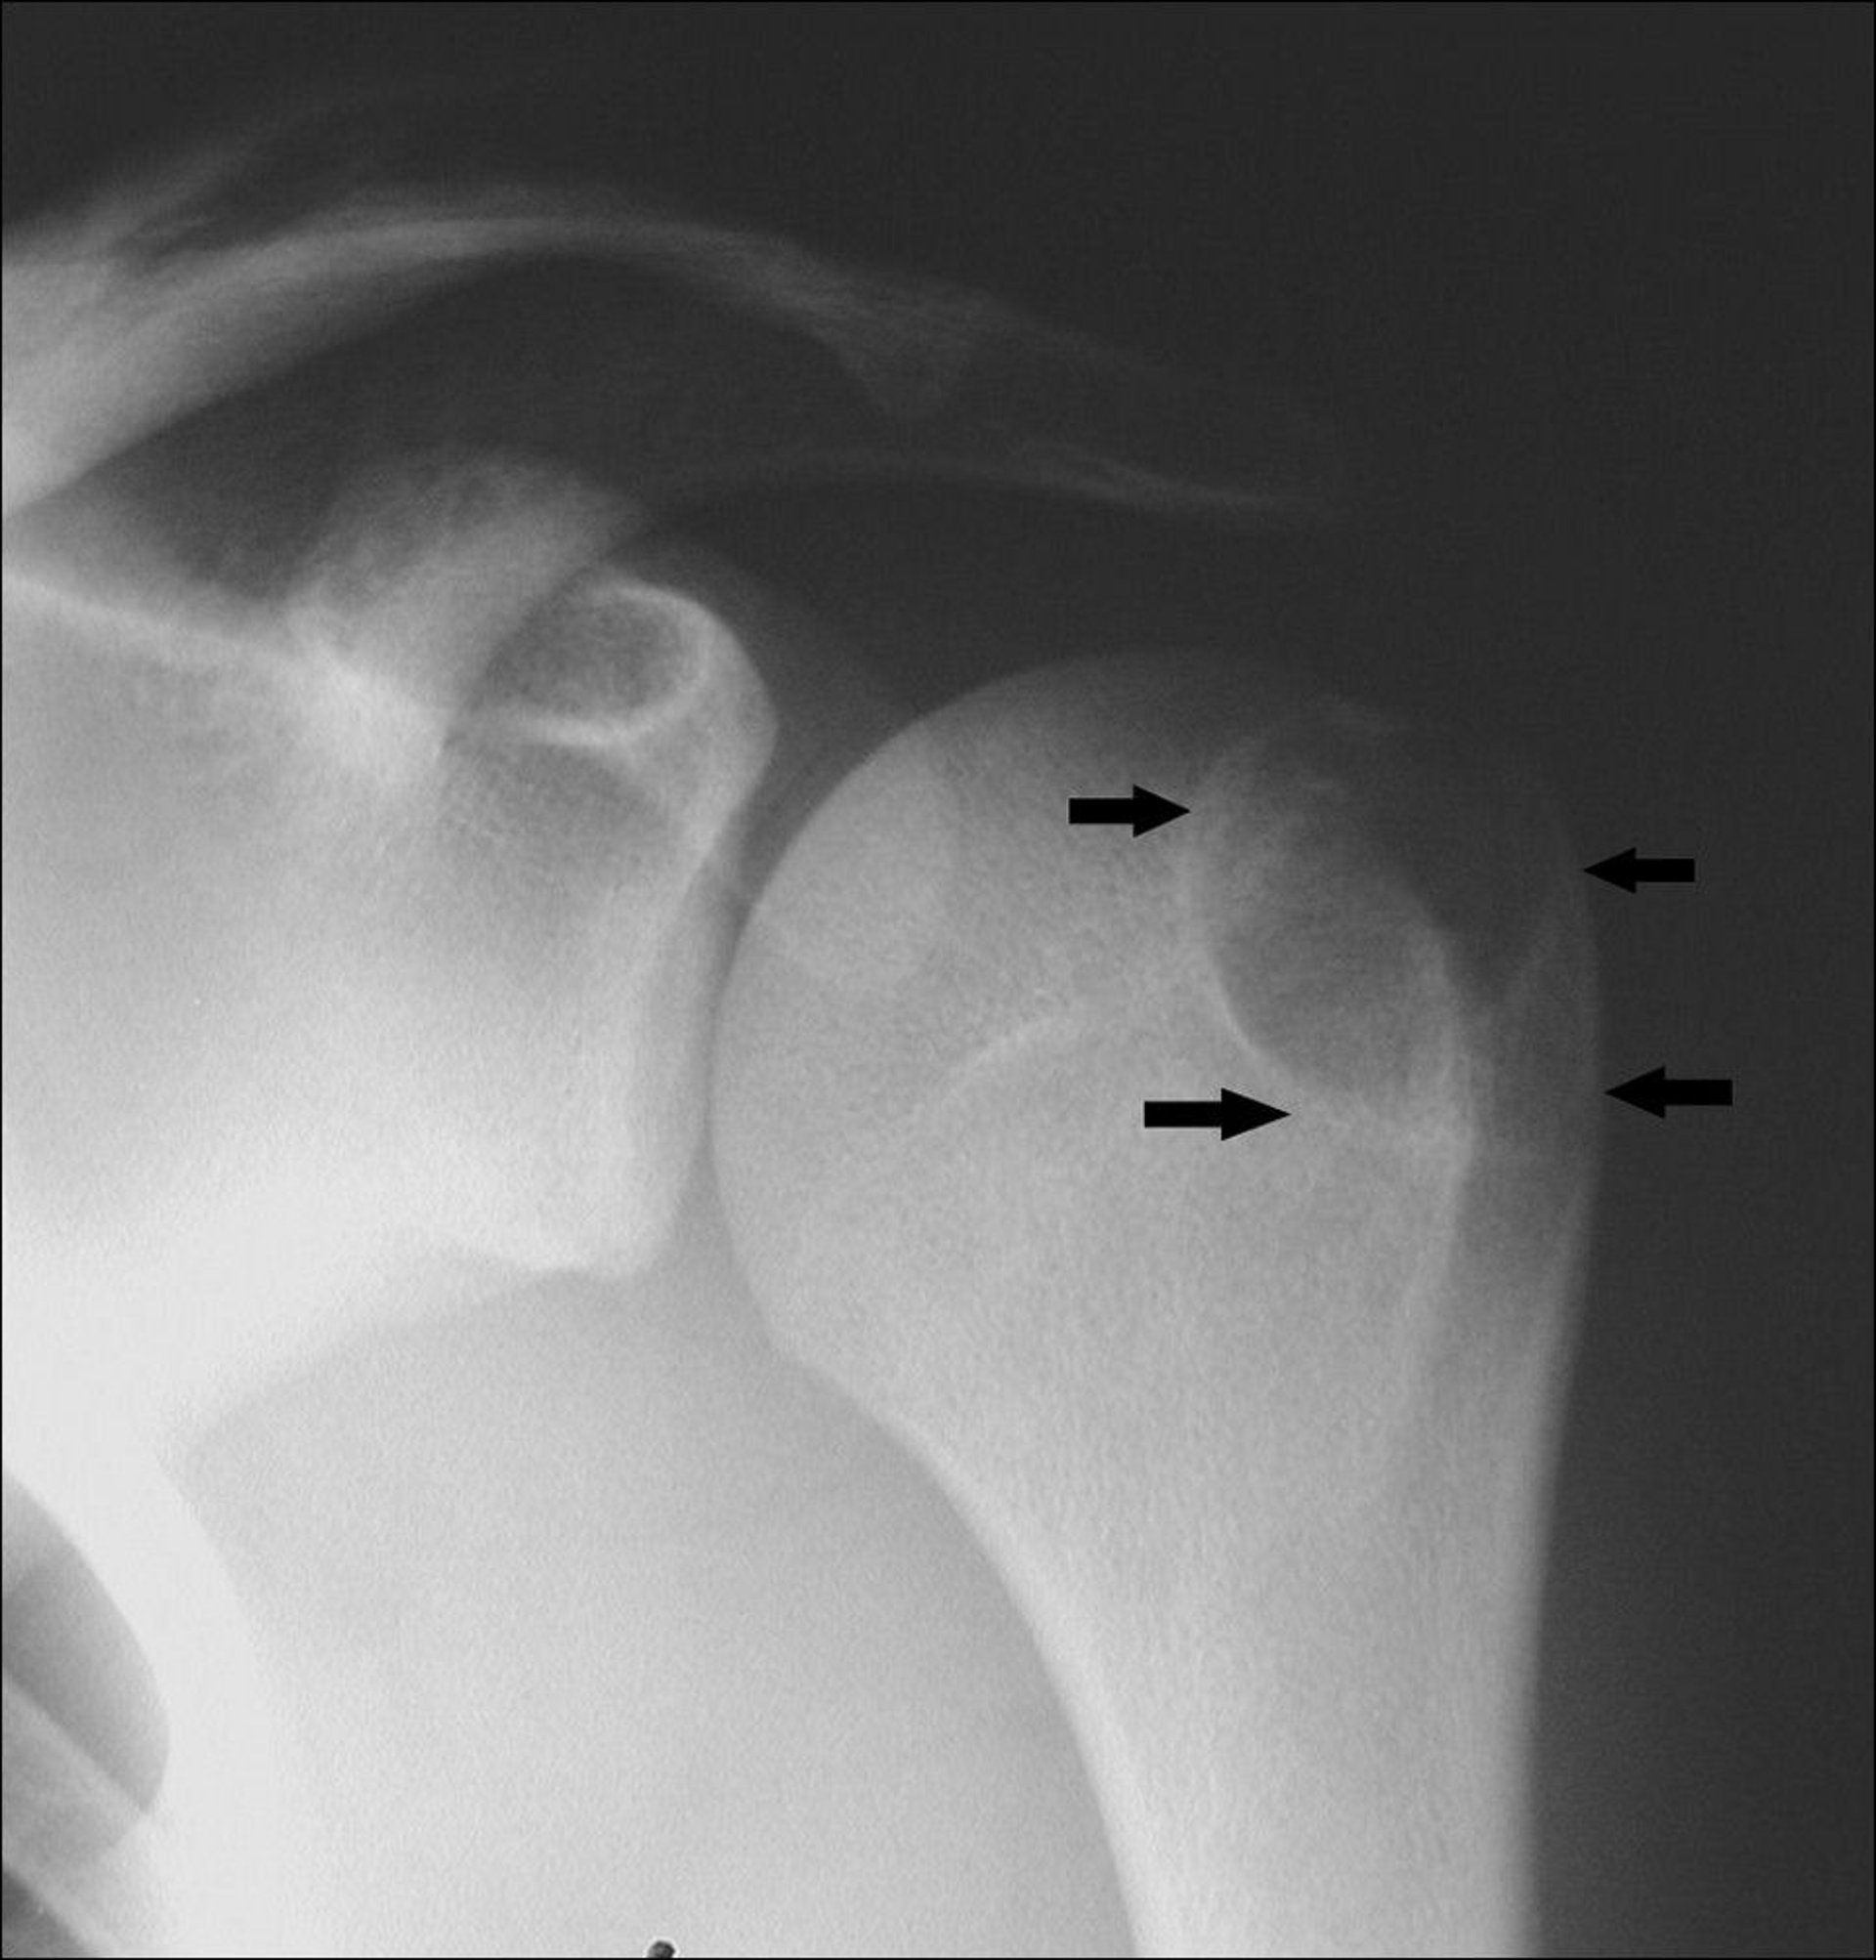

This shoulder x-ray shows a chondroblastoma in the upper arm bone at the end of the bone (arrows).

Image courtesy of Michael J. Joyce, MD, and Hakan Ilaslan, MD.